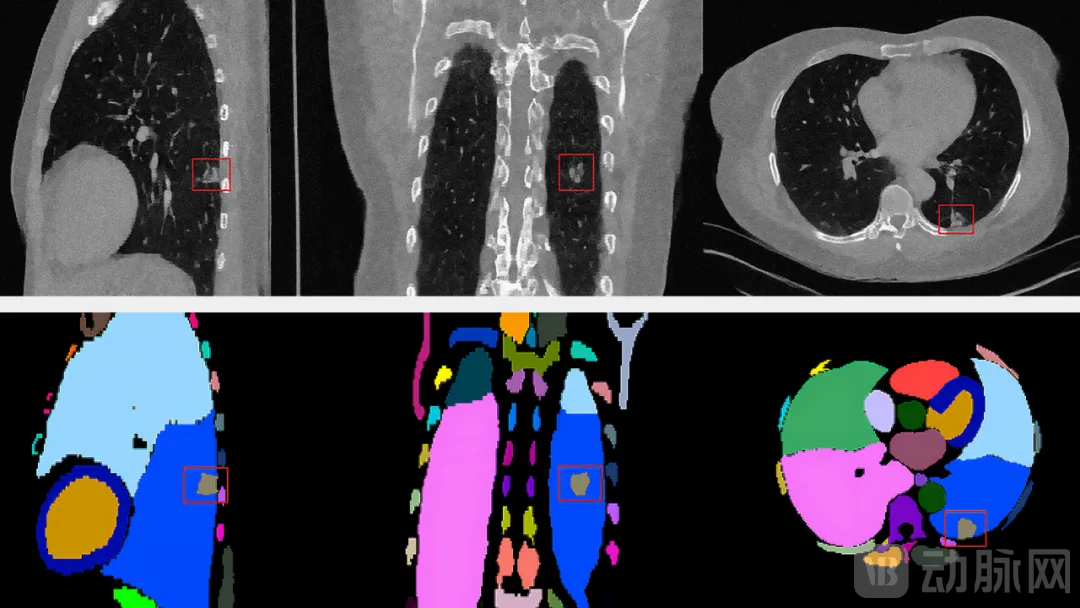

NVIDIA MONAI 现在提供一个全新生成式 AI 模型 MAISI(医学合成影像 AI),其能够生成多达 132 个解剖类别的高分辨率 CT 图像(512 × 512 × 512)。该模型通过在实际图像数量有限的情况下生成多样化逼真数据集来强化数据增强。它通过自动生成详细的影像和标签等来简化注释过程。该模型为使用敏感的患者数据提供了一种合乎伦理的替代方案。NVIDIA 将在今年晚些时候推出一个用于自定义的微调工作流,使用户能够针对特定任务完善该模型。

VISTA-3D(多功能影像分割和注释)模型是该平台的基石,以准确性、通用性和交互性著称。令人激动的是,VISTA-3D 在此次更新后覆盖 130 个类别。该模型已在标记和未标记数据上进行了训练。通过在额外数据集上进行持续训练和全面评估,该模型的性能得到了提升。